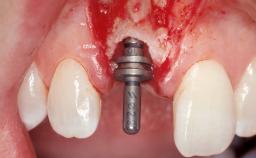

Early Placement of an Implant in a Maxillary Right Central Incisor Site

This 41-year-old female patient was referred to the clinic for the replacement of the right central incisor, since the tooth had developed a root fracture in the long axis that made extraction necessary. The healthy, non-smoking patient was first seen with the tooth still in place. A detailed Esthetic Risk Assessment was performed.The patient was worried about her dental esthetics and had high expectations for a successful treatment outcome from an esthetic point of view. The patient had a medium lip line that displayed parts of the gingiva in the anterior maxilla upon smile.

Type of Implants Two-Piece

Bone Augmentation Horizontal|Simultaneous

Augmentation Materials Autogenous chips|Xenogenous|Membrane

Bone Volume Deficient horizontally, allowing simultaneous augumentation

Loading Protocol Conventional or early